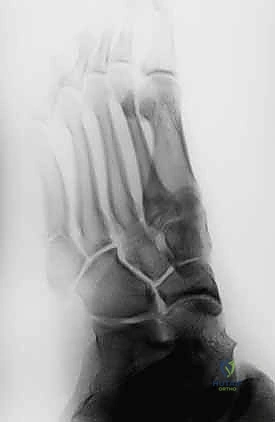

- التصوير بالأشعة السينية (X-rays): هي الخطوة الأولى والأساسية. يتم أخذ صور بأوضاع مختلفة (أمامية، جانبية، ومائلة) لتحديد موقع الكسر وشكله بدقة.

- الشق الجراحي الدقيق (Minimally Invasive): لا يقوم الدكتور هطيف بفتح شق كبير، بل يُحدث شقاً صغيراً جداً (حوالي 1 إلى 2 سم) عند قاعدة العظمة الخامسة لمشط القدم. هذا الشق الصغير يقلل من الألم بعد العملية ويسرع التئام الجرح ويحافظ على الشكل الجمالي للقدم.

- إدخال المسمار التيتانيوم (Screw Insertion): يتم اختيار مسمار طبي من التيتانيوم (طوله وسمكه محسوبان بدقة لتناسب عظمة المريض). يتم إدخال المسمار ليربط بين جزئي الكسر، مما يولد قوة ضغط (Compression) تجعل حواف العظم متلاصقة تماماً، وهو السر وراء الالتئام السريع.

- الإغلاق التجميلي: يتم إغلاق الشق الصغير بغرز تجميلية، ووضع ضمادة معقمة وحذاء طبي لحماية القدم.